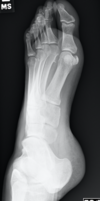

Bico talar

Coalizão calcaneonavicular.